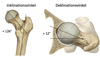

Var finns tuberculum minus på de bägge bilderna?

- På bilden är tuberculum minus närmst kroppen på bilden till vänster (triangeln) och till höger är tuberculum minus in mot revbenen

Vilka fyra funktionella delar har proximala humerus?

Caput med sin glidyta, tuberculum major/minor och skaftet